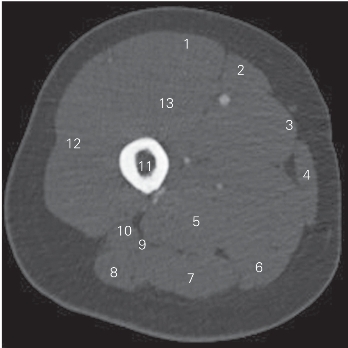

图5-8 经股骨上份的横断层CT图像(骨窗)

1 股直肌 rectus femoris 2 股内侧肌 vastus medialis

3 缝匠肌 sartorius 4 股薄肌 gracilis

5 大收肌 adductor magnus 6 半膜肌 semimembranosus

7 半腱肌 semitendinosus 8 股二头肌长头 long head of biceps femoris

9 坐骨神经 sciatic nerve 10 股二头肌短头 short head of biceps femoris

11 股骨 femur 12 股外侧肌 vastus lateralis

13 股中间肌 vastus intermedius